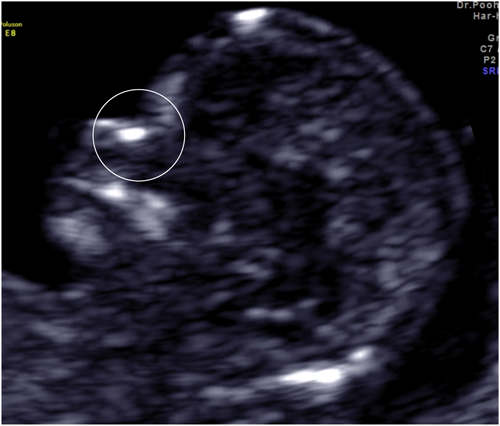

Fig. 2 Nasal bone

High echoic line on the nose of the fetus in sagittal section (circle).